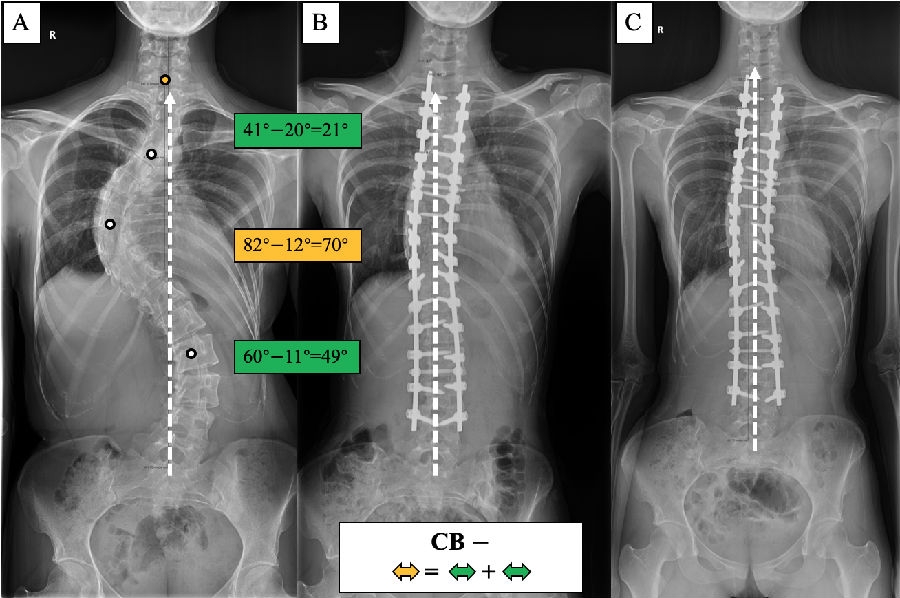

五、顶椎位置修正对手术矫形方案的指导意义

(1)术前CB患者,对称矫形:主弯矫正幅度=代偿弯矫正幅度之和。

图8. 各类型患者的手术矫形策略。

(1) 术前CB-患者:主弯矫正70°,上胸弯及腰弯矫正分别为21°和49°,术后维持平衡状态。